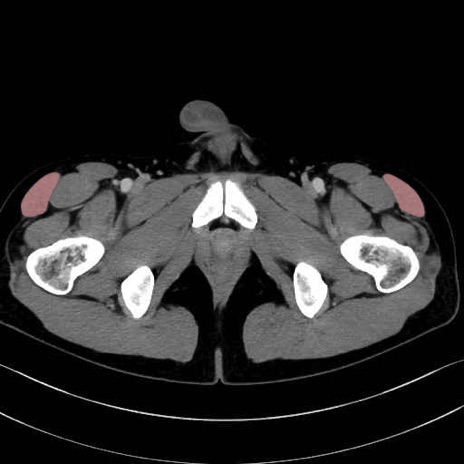

大腿筋膜張筋 (Tensor fasciae latae)